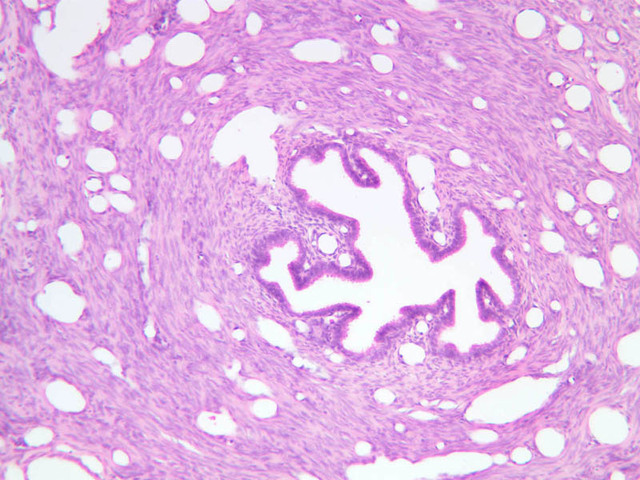

The resting or inactive mammary gland consists of predominantly dense connective tissue with small clusters of ducts and a few glandular elements (slide A-93 [2.5x-labeled, 10x, 20x, 40x] [1x, 2.5x, 10x, 20x]). It is difficult to differentiate between small ducts and alveoli as each is lined by simple low cuboidal cells. Lobes and lobules are not well defined. During puberty, predominantly under the influence of the ovarian hormone estrogen, the glandular or epithelial ducts proliferate and begin to differentiate into clusters of ductal and alveolar units termed terminal ductal lobule units (TDLUs). The non-pregnant gland will form multiple TDLUs that will not fully differentiate until pregnancy-induced growth. TDLUs are classified into Type I, Type II and Type III based on density of the ductules within each lobular unit. Type I and Type II lobules are typical of inactive glands that have not undergone a pregnancy cycle. Type III lobules are seen only in active glands or in inactive glands that have been through a pregnancy. Intralobular connective tissue is loose connective tissue that surrounds the alveoli and ducts within a lobule. The interlobular connective tissue is dense and contains considerable adipose tissue.